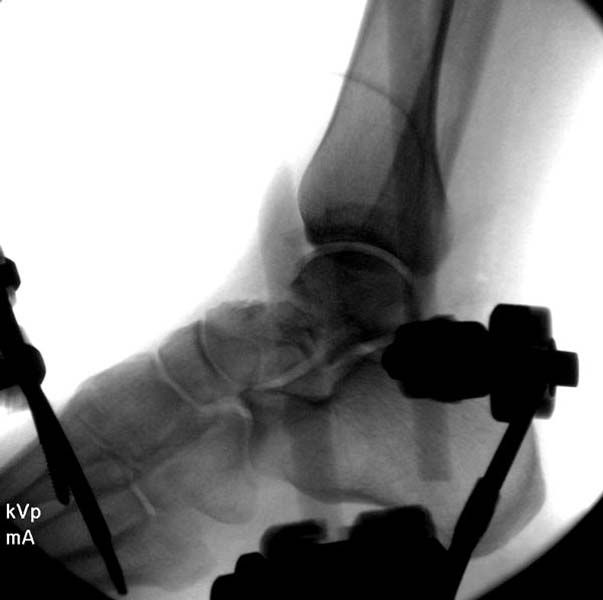

Больная стабильная после хирургических мероприятии и получив добро, приступили к закрытому вправлению таранной кости с укладкой наружного фиксатора. Затем укладка больную на бок и открытый остеосинтез перелома-вывиха головки бедра.

После спадения отека на стопе произведена фиксация тарана. Кстати, коллеги пересмотрели первоначальную консультацию по позвоночнику и на двух уровнях провели фиксацию. Из-за длительного постельного режима без нагрузки таз не стали оперировать...